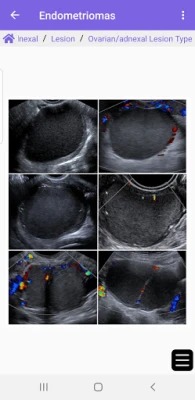

Aplikacja ACR® Guidance App zapewnia interaktywny, mobilny dostęp do wybranych wytycznych klinicznych ze strony internetowej ACR. Oferuje karty reakcji na kontrast ACR, systemy raportowania i danych (RADS) oraz treści dotyczące przypadkowych znalezisk (IF). To kluczowe źródło informacji dla profesjonalistów.